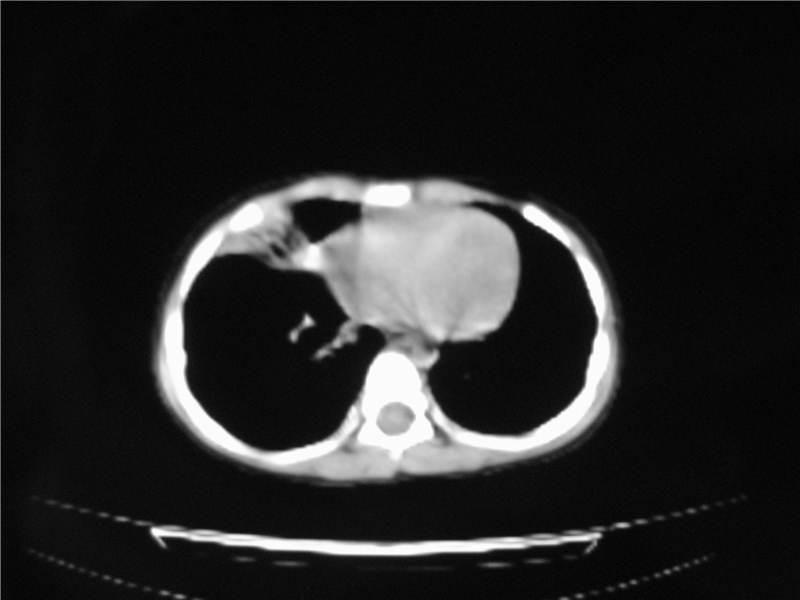

右肺中叶及下叶内段大片实变密度增高影,可见支气管气象,肺炎.

阻塞性肺炎及膨胀不全

摄吸气及呼气相对比片,本例为有肺中叶阻塞性炎症、不张,右肺下叶阻塞性炎症。

1)右肺炎症并右肺中叶肺不张,右肺上叶充气不良。2)右侧支气管异物不排除。

结合临床考虑支气管异物并阻塞性肺炎、肺不张。